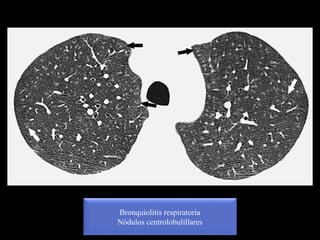

Neumonitis por hipersensibilidad subaguda

Nódulos centrolobulillares

Nodulos centrolobulillares

Bronquiolitis respiratoria